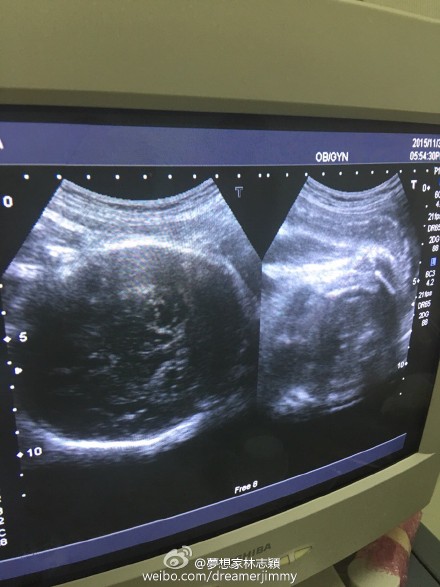

林志穎陪老婆做產檢 曬B超照雙胞胎很健康

11月30日晚,林志穎通過微博曬出老婆的B超照,并給大家報平安,寫道:“陪老婆產檢,baby很健康!”

林志穎曬雙胞胎B超照

新浪娛樂訊 11月30日晚,林志穎通過微博曬出老婆的B超照,并給大家報平安,寫道:“陪老婆產檢,baby很健康!”此微博曝光后,網友紛紛留言囑咐要好好照顧老婆和兒子。

早前,林志穎為了慶祝微博粉絲破六千萬,公布妻子懷孕喜訊,并透露是雙胞胎,預產期是在12月,會在臺灣剖腹生產。近日,林志穎在微博曬快餐店的自拍照,透露是為孕妻買夜宵,并稱老婆特別能吃。(我是彌爾)